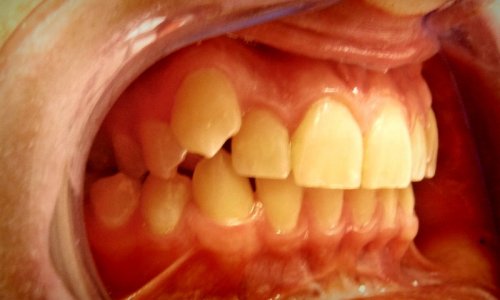

Zgryz Przed

Wada Zgryzu

Zbliżenie Przed

Ustawienie Zębów

Stan wyjściowy: Pacjent zgłosił się z problemami estetycznymi i czynnościowymi zgryzu.